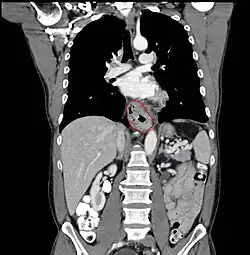

Anatomy

- AJCC divisions of the esophagus: (These are based on adjacent surgical landmarks)

- Cervical esophagus:

- Hypopharynx to the thoracic inlet, which is at the level of the sternal notch.

- By endoscopy, 15 to <20 cm from the incisors

- If thickening of the esophageal wall begins above the sternal notch, the location is cervical

- Upper thoracic esophagus:

- Thoracic inlet to lower border of the azygos vein

- By endoscopy, 20 to <25 cm

- Middle thoracic esophagus:

- Lower border of the azygos vein to the inferior pulmonary veins

- By endoscopy, 25 to <30 cm

- Lower thoracic esophagus and EG junction:

- Inferior pulmonary veins to the stomach; includes the intraabdominal portion of the esophagus

- By endoscopy, 30 to 40 cm